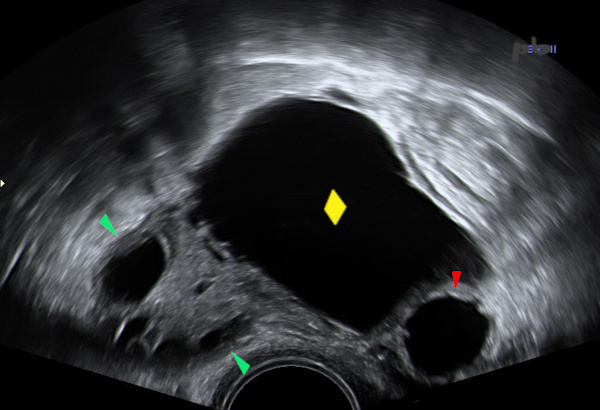

4 – Hydrosalpinx

Echographie endovaginale.

Kyste (♦) paraissant intra-ovarien (d’après l’angle de raccordement inférieur).

En-dessous sur le cliché, une image liquidienne avec l’aspect de « roue dentée » (![]() ), en faveur d’un hydrosalpinx.

), en faveur d’un hydrosalpinx.

Ovaire (![]() ).

).

4 – Hydrosalpinx

Transvaginal ultrasound.

A cyst (♦) appearing intra-ovarian (based on the lower attachment angle). Below in the image, a fluid-filled structure with a « gear wheel » appearance (![]() ), suggestive of hydrosalpinx.

), suggestive of hydrosalpinx.

Ovary (![]() )

)